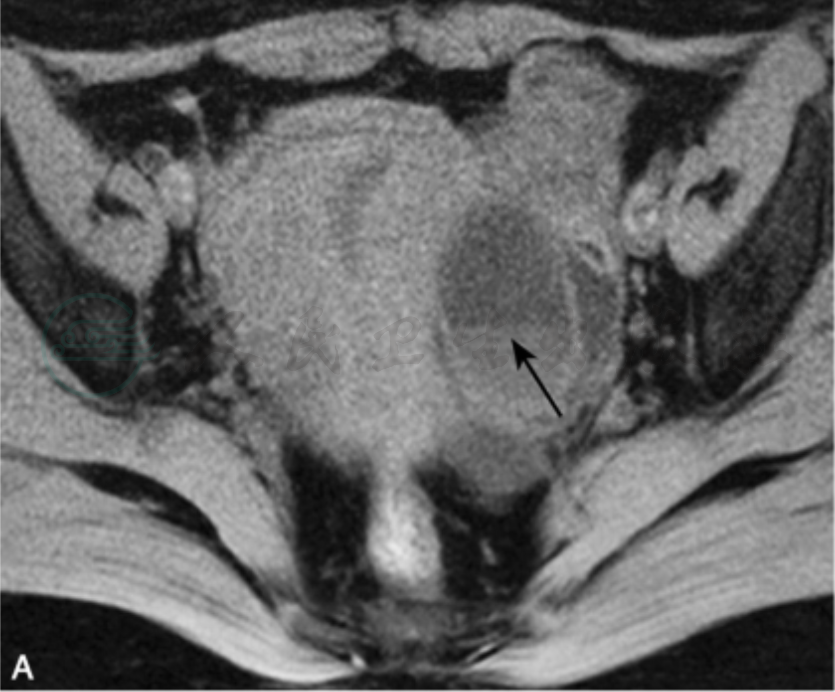

图1

女性,44岁,下腹痛一周,左侧输卵管积脓横断位T1WI脂肪抑制(A)、T2WI脂肪抑制(B)及矢状位T2WI(C)见左附件区粗细不均、扭曲折叠的管状结构(Ⅰ型),内见液-液平面(黑箭);增强(D)后可见管壁较均匀增厚(大于0.25cm)。DWI(E)(b值800)见囊液呈上低下高信号,囊液下部ADC值为1.35×10-3mm2/s。矢状位有利于观察病灶的整体形态。U:子宫。